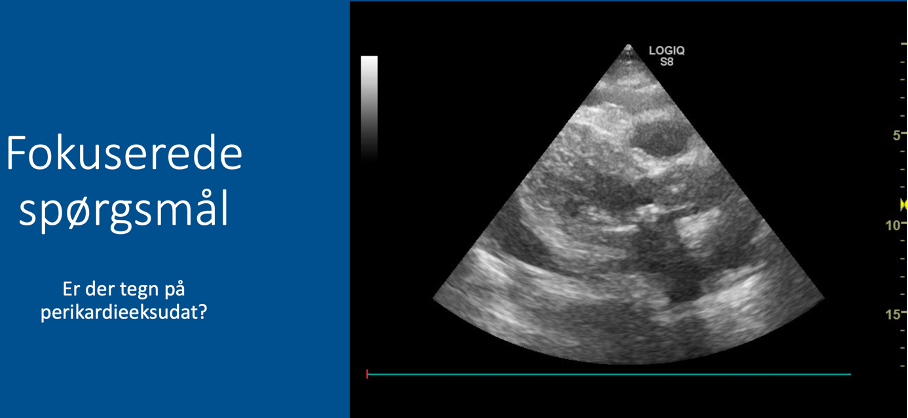

Q

Fokuserede spørgsmål (FHUS):

* Perikardieeffusion: ja/nej?

A